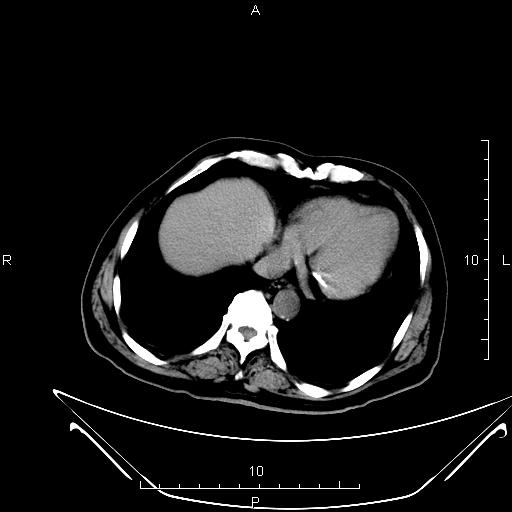

CT50218:上腹部CT

男,76岁,上腹部不适半个月。

胰头部可见不规则低密度占位,不均匀强化, 肝内可见多发斑片结节低密度影,斑片灶不同期,可见不同程度强化,部分结节强化不明显,脾大,考虑胰头占位---胰腺癌伴肝内转移可能性大。

胰头囊腺癌伴肝内转移可能性大。

肝右叶海绵状血管瘤,胰头囊腺瘤可能。